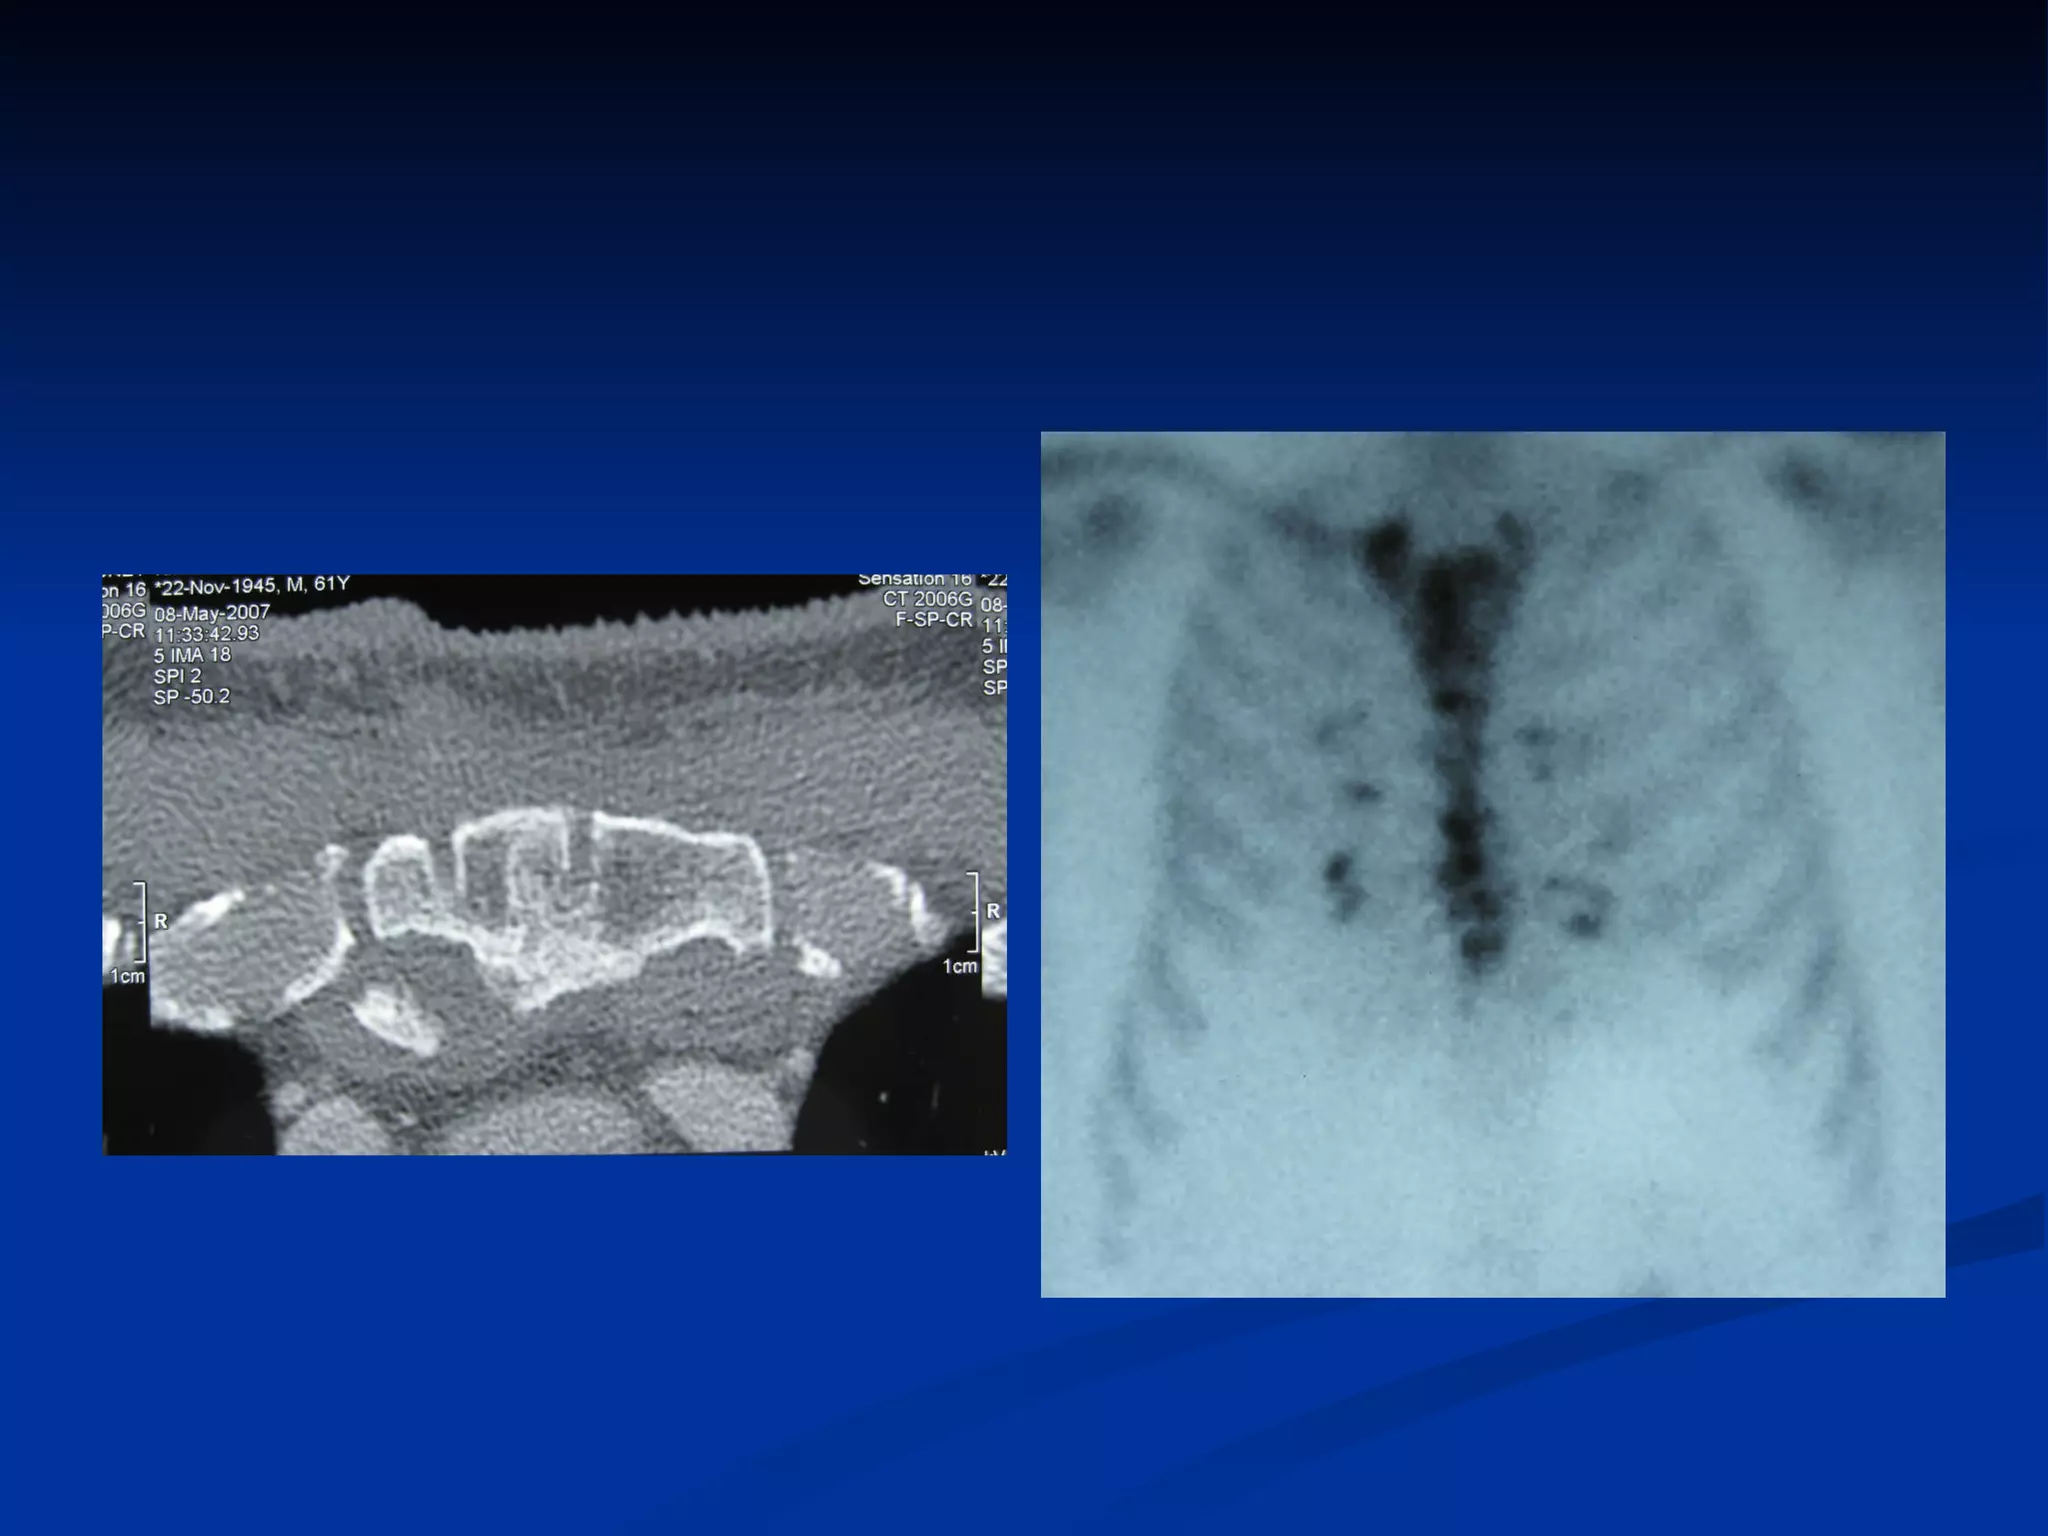

How to make an early diagnosis The  Classic symptoms  and signs of acute infection are  infrequently  encountered   Fever and Leukocytosis  in the absence of local symptoms or signs may be the only presenting clinical features in a small percentage of patients  Wound discharge  is the most common presentation and occurs in 70% to 90%  Local symptoms include wound pain, tenderness, and sternal instability  Chest roentgenograms  are rarely helpful in the early diagnosis  Chest computed tomography scanning with mediastinal aspiration

Osteomyelitic Sternum

How to makean early diagnosis The Classic symptoms and signs of acute infection are infrequently encountered Fever and Leukocytosis in the absence of local symptoms or signs may be the only presenting clinical features in a small percentage of patients Wound discharge is the most common presentation and occurs in 70% to 90% Local symptoms include wound pain, tenderness, and sternal instability Chest roentgenograms are rarely helpful in the early diagnosis Chest computed tomography scanning with mediastinal aspiration